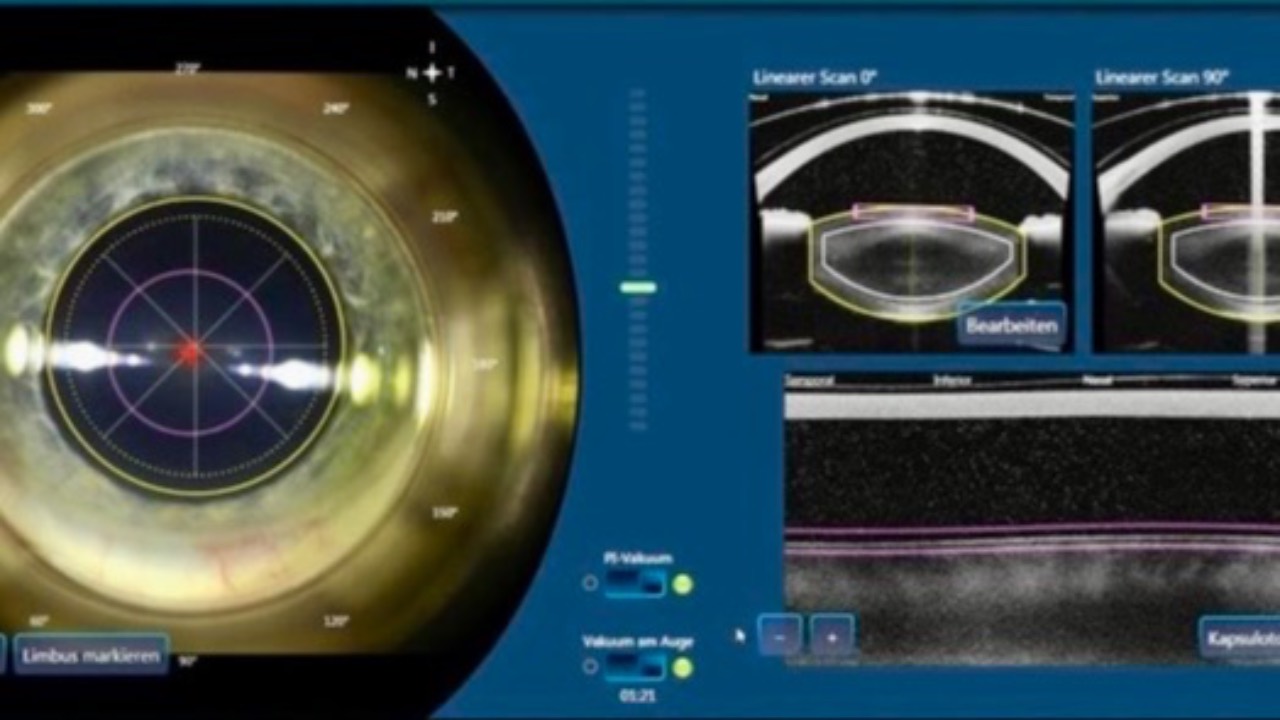

Astigmatism: FEMTO vs TORIC IOLs

Why do you choose what you choose?...

A randomized clinical trial published this week compared the efficacy of femtosecond laser arcuate keratotomy (FLAK) versus toric intraocular lenses (IOL) in cataract surgery patients with corneal astigmatism.

Important outcomes were looked at, including vis...